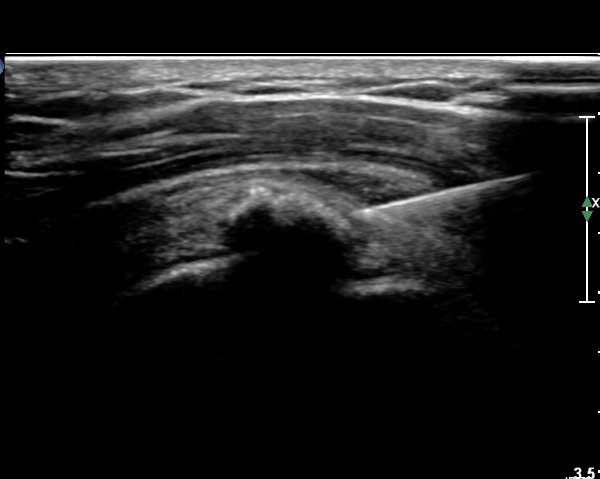

±Ø»ó°Ç Ⱦ´Ü¸é°Ë»ç¿¡¼­µµ ±Ø»ê°Ç³» ¼®È¸È­ µ¢¾î¸®°¡ °üÂûµÈ´Ù(»çÁø 2).

±Ø»ó°Ç Á¾´Ü¸é °Ë»ç»ó¿¡¼­ Á¡¾×³¶³»¿¡ ÁÖ»ç¹Ù´ÃÀÌ À§Ä¡ÇÑ °ÍÀÌ º¸ÀδÙ(»çÁø 3).